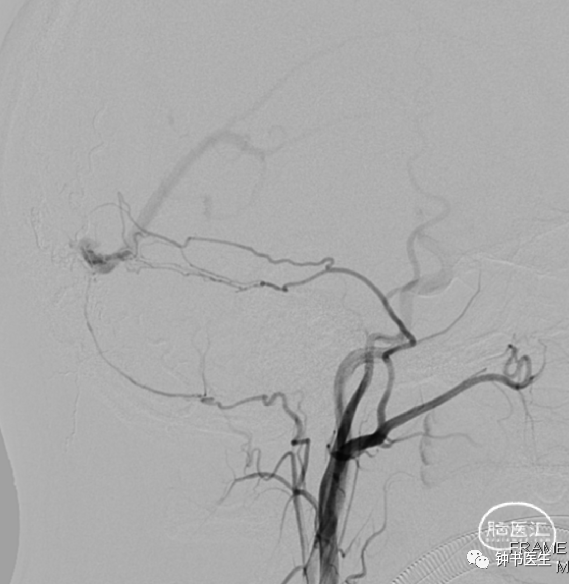

术前 DSA

R-ICA

术前DSA :右侧脑膜中动脉供血

R-MMA